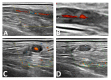

Giant cell arteritis is a medical emergency as severe, irreversible complications may occur if it is not treated in a timely manner. However, in daily practice early diagnosis can be challenging. We report the case of a 70-year-old woman who presented with multiple ischaemic cerebral vascular accidents related to newly diagnosed giant cell arteritis. Review of her charts revealed a substantial delay from the onset of symptoms to diagnosis. This case demonstrates the need for additional efforts to reduce delay in referring patients with giant cell arteritis and the need to implement fast-track clinics to prevent serious complications.